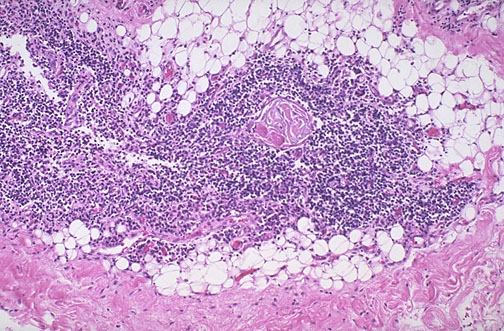

| Normal adult thymus is seen at low magnification. Beyond puberty, the thymus continues to atrophy, with decreasing numbers of lymphocytes, so that the adipose tissue becomes more prominent. Occasional Hassall's corpuscles appear in the lymphoid areas. |